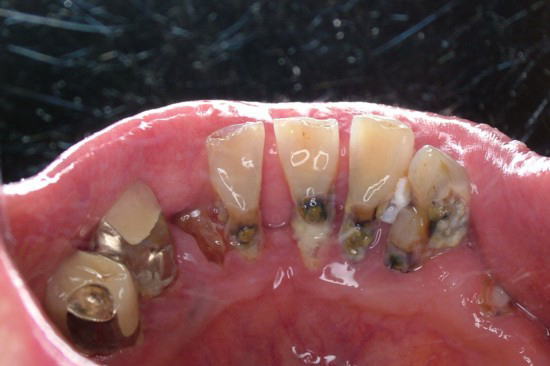

下顎前歯に見られる根面う蝕